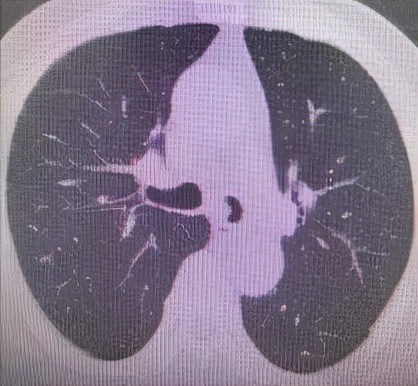

于世寰主任介绍到,患者气管分叉处占位病变面积较大,已累及左、右主支气管,从肺CT影像上判断隆突区病变导致左主支气管狭窄约70-80%左右、右主支气管狭窄约50-60%左右,可操作空间十分有限,支气管镜介入治疗难度较大。隆突区占位病变已累及左右主支气管导致了呼吸困难已不适宜行外科手术治疗,必须通过支气管镜削瘤治疗来解除病人因气道梗阻导致的呼吸困难。支气管镜削瘤治疗与开胸外科手术相比,有痛苦小、创伤小、花费少、可重复性强、并发症少等优点。

肺 部 C T (削瘤前)